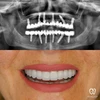

Zirconium Applications

Porcelain Applications

Laminate Veneer